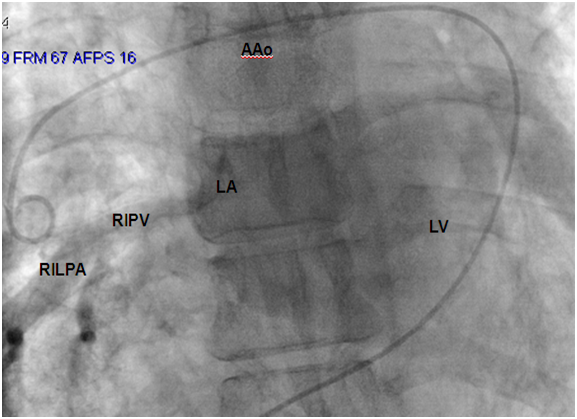

Figure 3: Dilated RIPV drained to LA. AAo: Ascending Aorta; LA: Left Atrium; LV: Left Ventricle; RIPV: Right Upper Pulmonary Vein; RILPA: Right Inferior Lobar Pulmonary Artery.

Pulmonary hypertension, possible coexistent congenital heart disease and anatomy of anomalous venous return required cardiac catheterization including pulmonary angiography. Hemodynamic study showed a moderate pulmonary hypertension predominating on the left side. Blood gas analyses did not provide any signs of cardiac shunt (Table 1). Venous angiography confirms cardiac CT findings (Figure 3-5). The patient was discharged with inhaled corticosteroids and betamimetics. Evaluation at 6 months did not show any sign of aggravation in term of stress tolerance